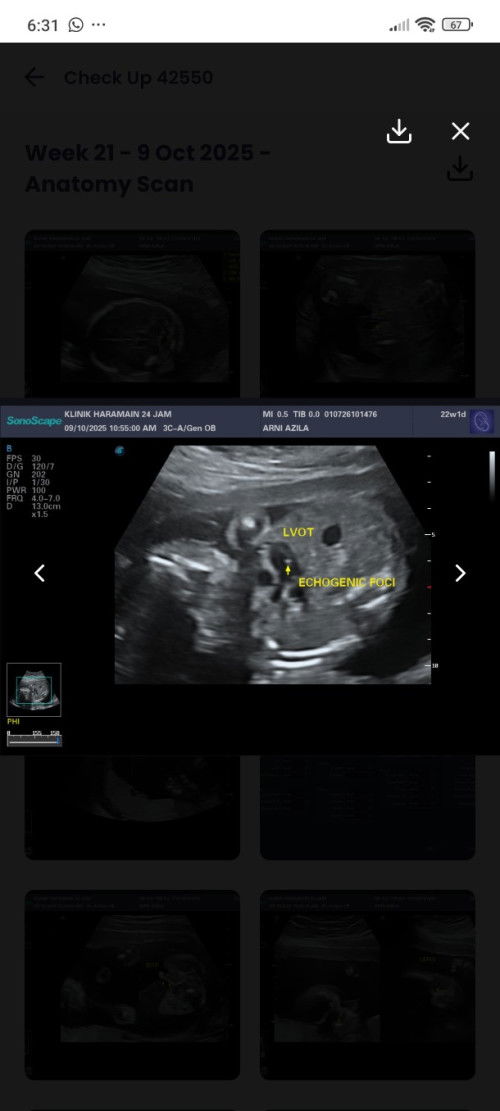

Lebihan otot di jantung baby

Hi,ada tak berpengalaman masa detail scan baby,ade lebihan otot di jantung baby??? Sono kata tak bahaya tapi kena follow up dgn doktor. Ada tak yg macamni,lepastu masa lahir nanti baby ok ke ? Risau la hmm.. tujuan tanya ni mungkin sy bole bersedia jika ada apa2 kemungkinan